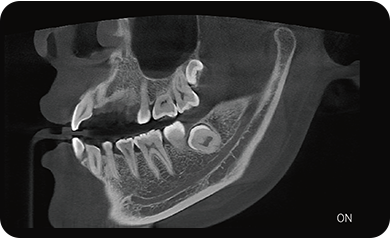

超能去伪 至臻影像

局部超清显示、 移动视野摄片

真人正侧位投影,实现CT成像区域无极可调

可根据临床需求任意调整成像区域大小实现局部超清三维显示

可根据临床需求任意调整成像区域大小实现局部超清三维显示

临床样片